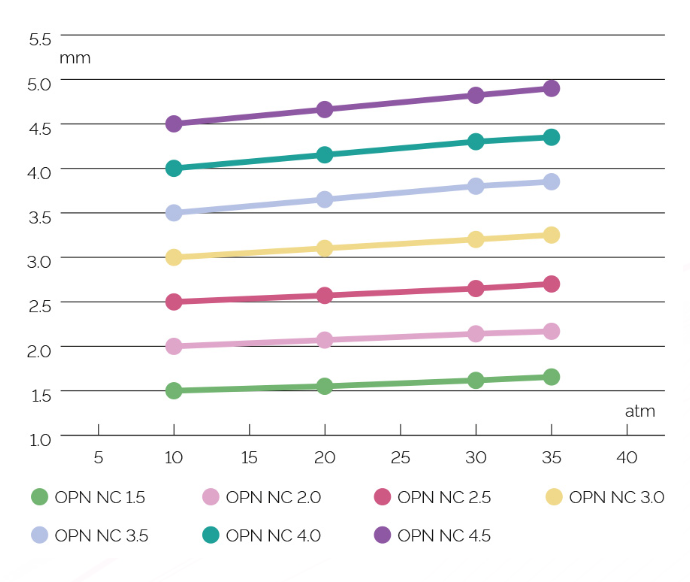

– Lineaarinen yhteensopivuuskäyrä jopa yli 40 atm

Markkinoiden alhaisin vaatimustenmukaisuus!

Vaatimustenmukaisuuskaavio: